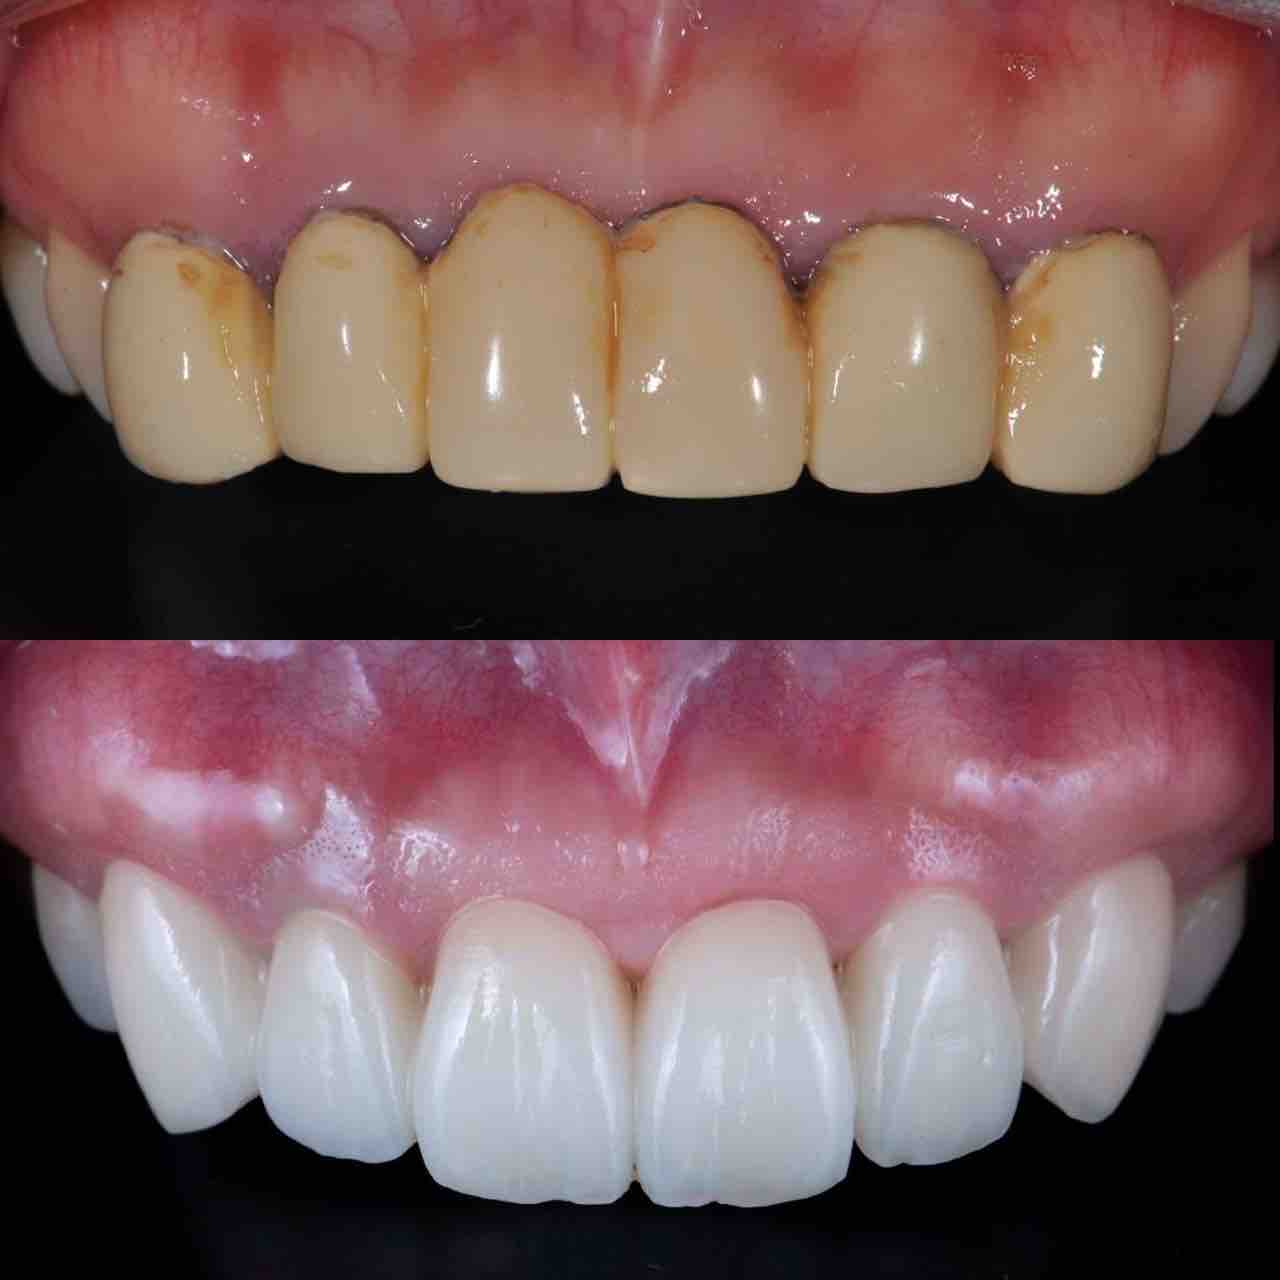

¥¤¥ó¥¹¥¿¥°¥é¥à¤ËºÜ¤»¤Æ¤¤¤ëÅö±¡¤Î¾ÉÎã¤Ç¤¹